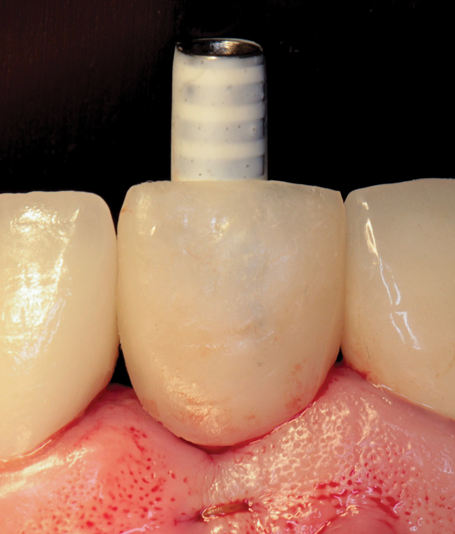

(38.) The opaqued titanium provisional abutment was gently tightened onto the implant.

Figure 38

(39.) The composite tooth shell was modified to fit around the abutment, positioned intraorally, and bonded to the abutment with flowable composite in the incisal half.

Figure 39